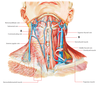

What are the 2 triangles of the neck?

Anterior and posterior triangles